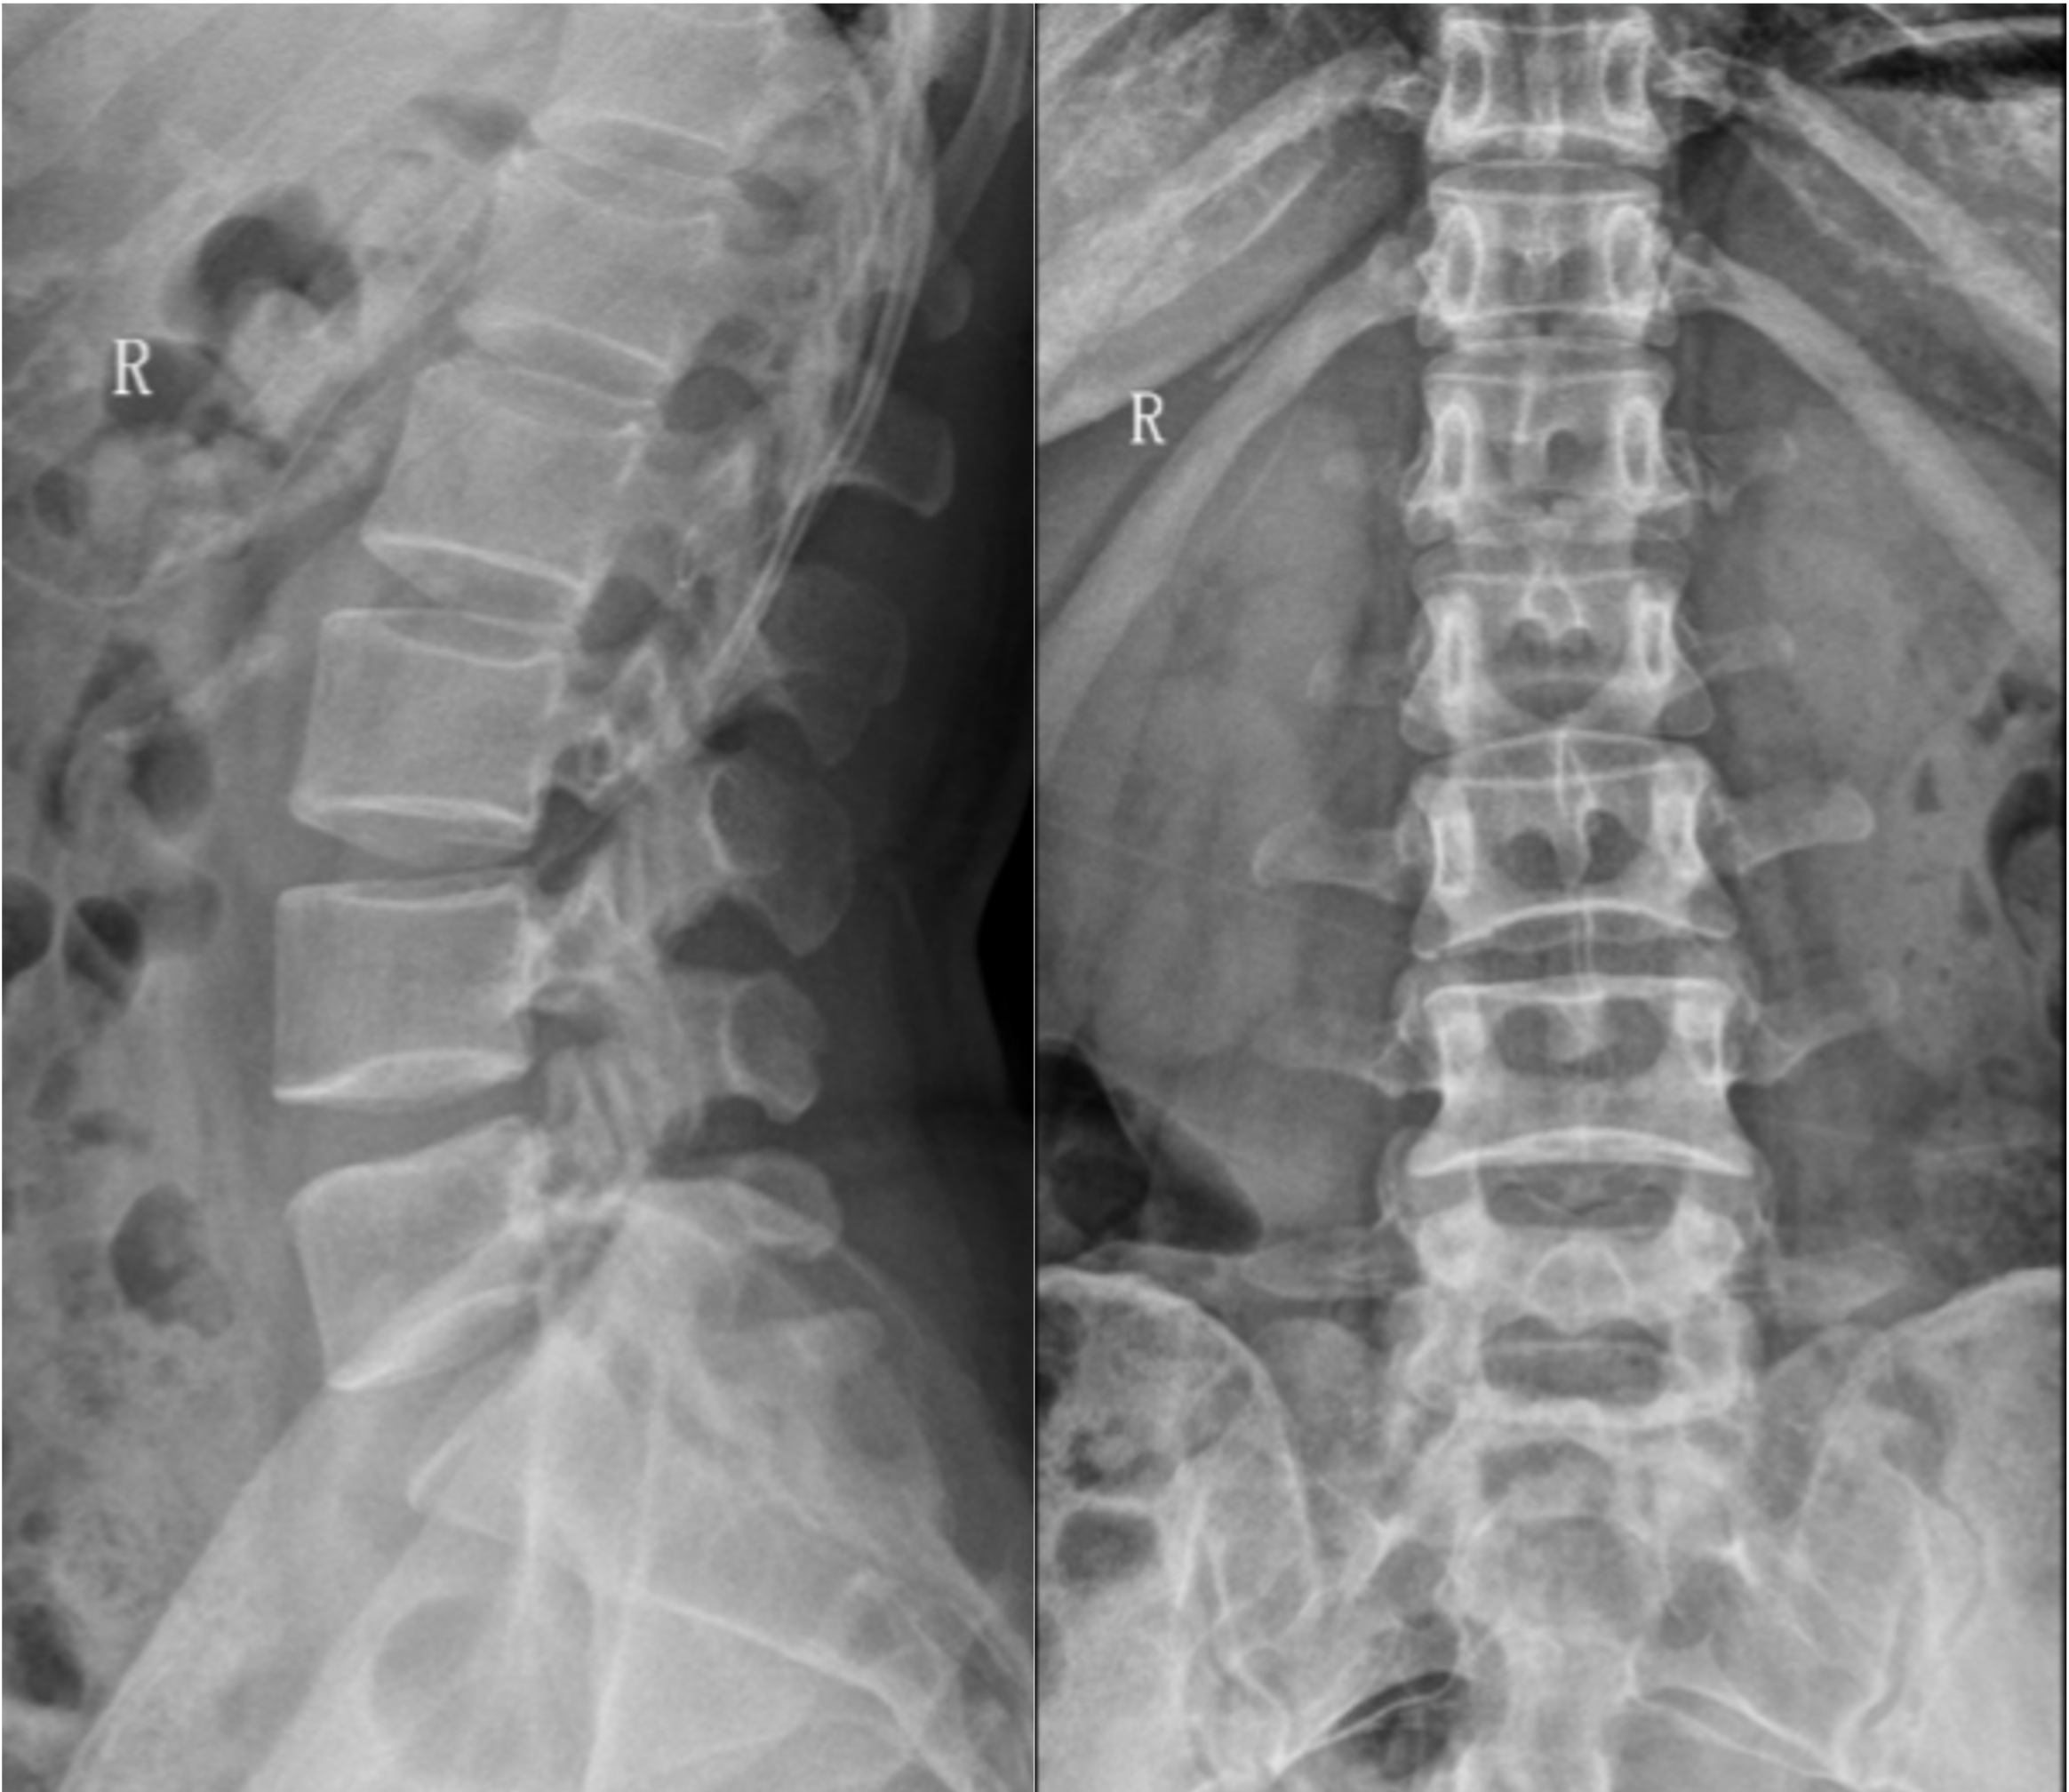

【影像】腰椎正侧位片示T12、L1压缩性骨折、L1横突骨折(陈旧性)。